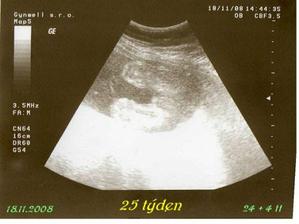

tak tohle album obsahuje vše co se týká našeho prvního miminka, které nosím pod svým srdíčkem, výbavičky co chystáme a co bychom chtěly nachystat.. Narodit se má 6.3.2009 , nevíme co to bude - asi necháme jako překvapení.